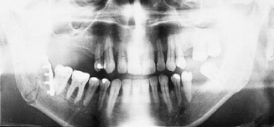

The primary purpose of the consultation is the outpatient follow-up treatment and care of patients who have undergone surgery following bone injuries to the upper and/or lower jaw. In addition to patients with fractures of the facial skull, patients with injuries to the teeth and facial soft tissues are also followed up.

Osteosynthesis procedures are performed at our clinic according to modern international standards. Mini and micro plates made of titanium and special medical steel are used to stabilize the fractured bones. Especially for the treatment of temporomandibular joint fractures a joint plate was developed in our clinic. The development and application of resorbable osteosynthesis materials is at the same time a research task of the clinic.